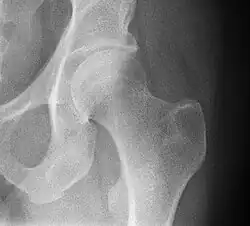

Superficies articulares

Está formada por una superficie cóncava que es el acetábulo y otra convexa, la cabeza femoral, por ello la articulación tiene una gran movilidad.

- Acetábulo o cavidad cotiloidea del coxal: ubicada en la cara externa del hueso, presenta una parte articular en forma de medialuna y una parte no articular que es el trasfondo de la cavidad. Está circunscrita por la ceja cotiloidea, en su borde inferior está interrumpida por la escotadura isquiopubiana. La cavidad cotiloidea está orientada hacia abajo y hacia delante.

- Cabeza femoral: fr superficie convexa, corresponde a dos tercios de esfera. En su centro presenta la fosita del ligamento redondo para la inserción de dicho ligamento. La cabeza femoral se mantiene unida a la diáfisis a través del cuello femoral, el cual está orientado hacia arriba, adentro y adelante.